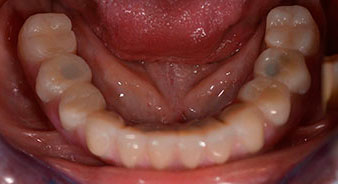

Направи се скенер с триизмерна компютърна томография (CBCT, Planmeca), за да се подпомогне планирането и да се намалят рисковете. Той показа, че качеството и количеството на наличната кост са достатъчни за операцията и имедиатното възстановяване, използвайки Fast & Fixed метод. Следвайки протокола за тази концепция, имплантите са поставени на 35, 32, 42 и 45 позиция. Ангулирането на дисталните импланти до 45° промени профила в задната зона и осигури по-голяма поддръжка в многоъгълната зона (Фиг. 3).

Ангулираните абатмънти (35°) са завити в имплантите, за да компенсират отклонението от дисталните импланти, така че в резултат профилът на разположение на всички импланти да е възможно най-перпендикулярен на нивото на захапката. Това е предпоставка за оклузално поставяне на временна и впоследствие на постоянна протеза (Фиг. 15 и 16).

След това е взет отпечатък и е определена захапката на пациента, за да може зъботехникът незабавно да започне изработването на временната протеза. Протезата е поставена в същия ден (Фиг. 17 и 18).

След изчакване на необходимото време за осеоинтеграция, финалният отпечатък на имплантите е свален и следователно е изработена финалната протеза (Фиг. 19 и 20). В този момент, лекарят по дентална медицина и пациентът могат да обсъдят дали да използват керамични или пластмасови фасети и циркониева или метална рамка. В този случай, екипът на д-р Паску избира пластмасови фасети, имайки предвид неясната прогноза относно частичното обеззъбяване в челюстта и фактът, че зъб 24 е прорастнал. Този вид протеза обикновено е по-лесна за адаптиране и впоследствие може да бъде променяна спрямо новата ситуация в челюстта.